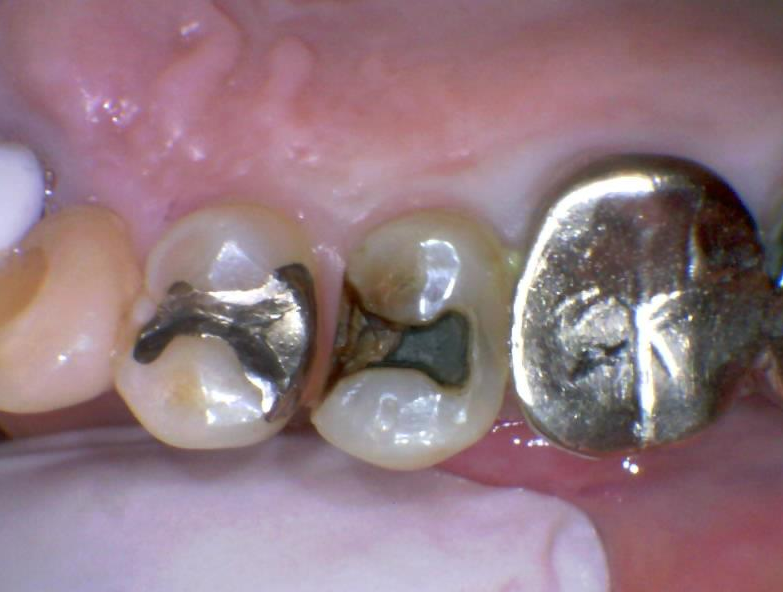

初診時の写真です。患者さんは銀歯が外れた以外には痛みなどの症状は特にありませんでした。銀歯は10年くらい前?に治療したものとのことでした。ぱっと見はただ銀歯が外れているだけに見えますが、実際はとても大きな虫歯になっています。